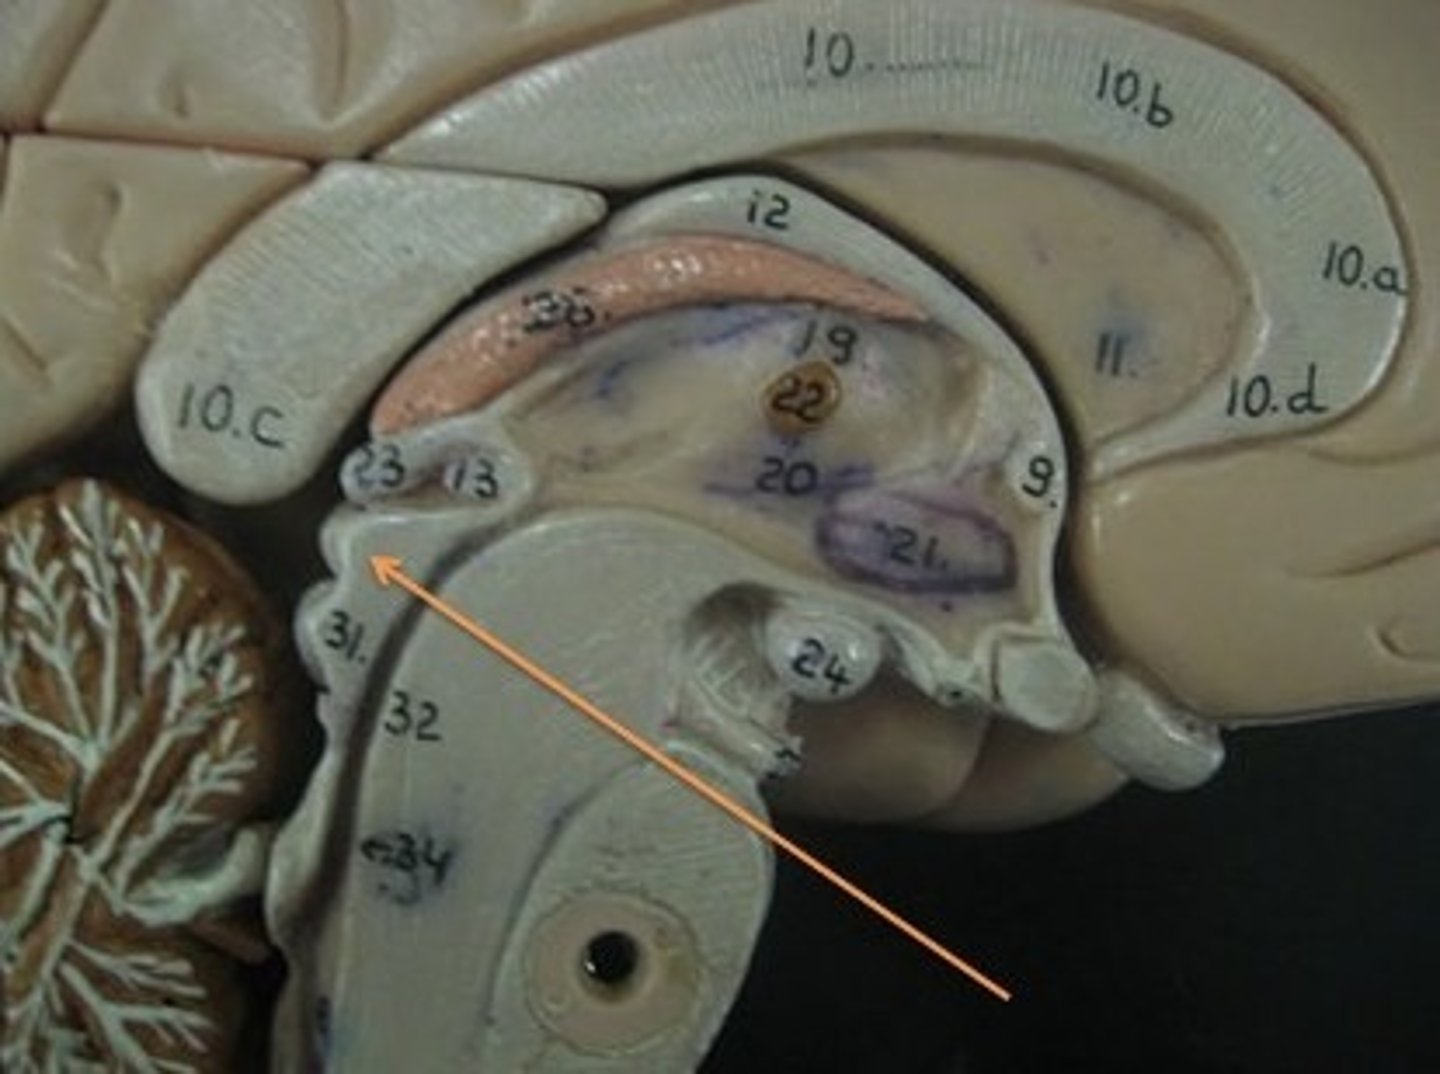

lateral ventricles

third ventricle

fourth ventricle

interventricular foramen

connects lateral ventricles to third ventricle

cerebral aqueduct

connects the third and fourth ventricles

choroid plexus

on the floor of all the ventricles, produces CSF

arachnoid villi

reabsorb/drain CSF into venous blood

diencephalon

thalamus and hypothalamus

thalamus

relay station for all somatosensory information

intermediate mass

connection between the two thalami across the third ventricle, dumbbell shape

hypothalamus

brain region (many nuclei) in charge of maintaining homeostasis

pituitary gland

produces hormones

mammillary bodies

olfactory relay stations

epithalamus

region above midbrain that contains pineal gland

pineal gland

regulates sleep-wake cycles, secretes melatonin

corpus callosum

the large band of neural fibers connecting the two brain hemispheres and carrying messages between them

septum pellucidum

membrane that separates lateral ventricles

basal nuclei

internal masses of gray matter, smooth out motor movement

fornix

band under septum pellucidum